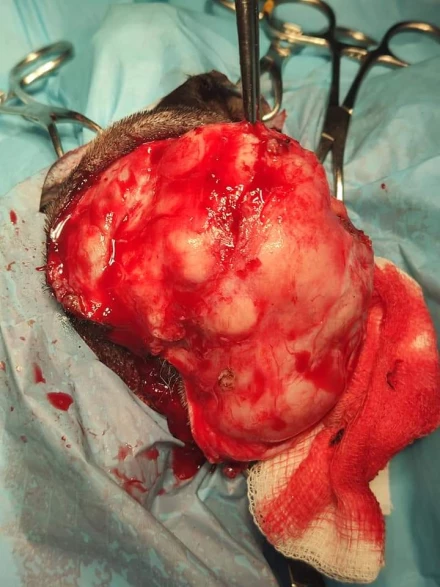

Operacja masywnej zmiany twarzoczaszki